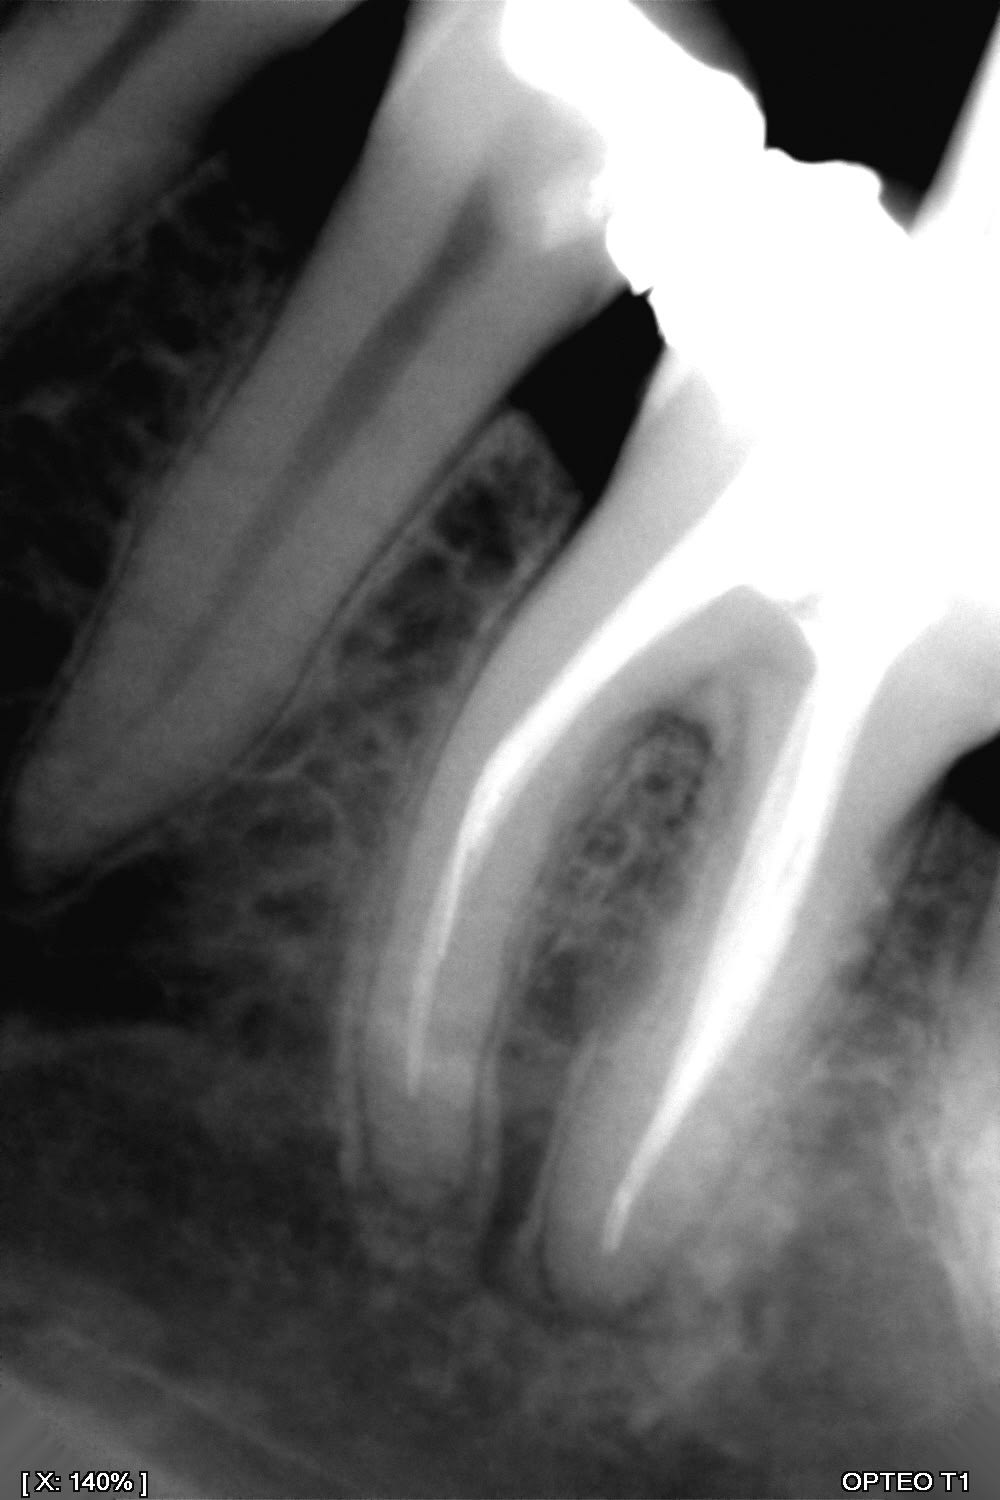

Désobturation endo ...peut être difficile voir la Rx

> Désobturation endo ...peut être difficile voir la Rx